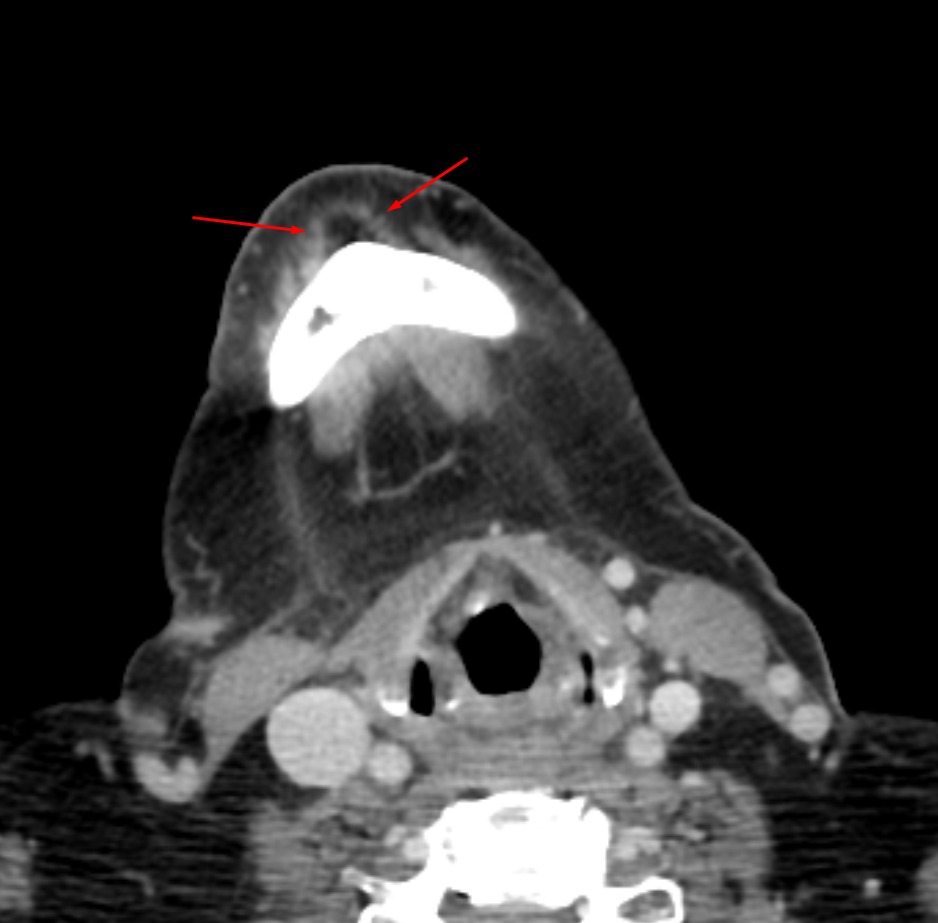

Age: 40

Sex: Male

Indication: Neck pain